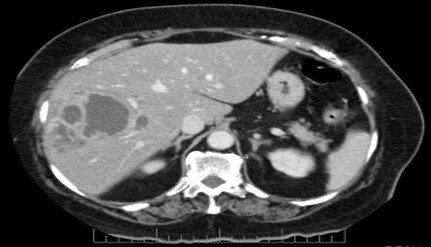

Hemangioma

–Most common benign liver SOL

–Well-defined hypodense lesion on NCCT

–Peripheral nodular discontinuous arterial enhancement

–Progressive centripetal fill-in on delayed phase

–No washout, no capsule